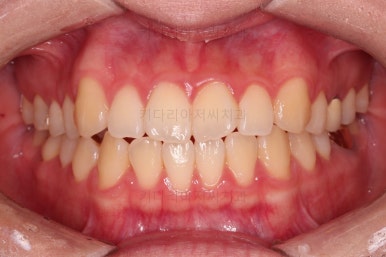

5. 치료의 종료

부산치아교정잘하는곳 키다리아저씨치과에서 치료를 종료했을 때의 사진입니다.

위아랫니가 가지런해졌고요.

다시 틀어지지 말라고 적절한 유지장치를 구성합니다.

보철 치아의 위치/크기로 인해 100% 중앙선은 맞기 힘드나 가장 잘 맞추어 놨고, 앞니의 각도도 매우 좋아졌습니다.

아래 앞니도 단순히 머리 부분만 뒤로 눕힌 것이 아니라 뿌리까지 뒤로 당겨왔고요.

6. 전후 사진 비교

교합, 가지런함, 앞니 각도 모두 좋아졌습니다.